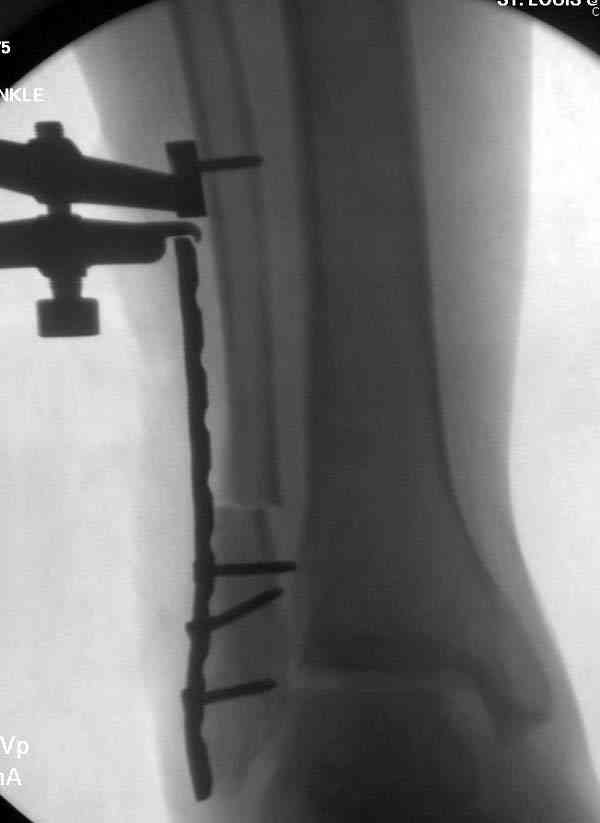

Здесь представлено решение похожей проблемы. Больной в течение года лечился консервативными мерами, и боли в голеностопе были основным показанием к операции.

Проведена обычная стандартная процедура по исправлению неудовлетворительного состояния голеностопного сустава, где кроме удлинения малоберцовой с применением compression tension device за проксимальный конец пластины, проведено замещение трикортикальным графтом из крыла, освобождение синдесмоза и медиальной щели от

фибротических масс с фиксацией.

Дополнительно у больного плоская стопа, во время операции провели небольшую скользящую остеотомию, надеемся, что поможет.